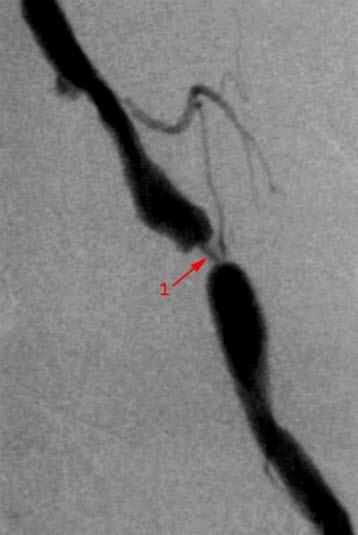

Undersøkelsen gjør det mulig å påvise skader, forsnevringer, blokkeringer, utposninger (aneurismer) på årene, og viser også blodtilførselen til de organene eller områdene blodårene forsyner.

Ved den spesielle typen hjerneblødning som kalles subaraknoidalblødning, der det går hull på en utposning av blodåren (aneurisme), brukes arteriografi. Arteriografi brukes også til å undersøke utposninger i andre arterier, for eksempel hovedpulsåren (aorta). Det kan også være aktuelt å gjøre arteriografi før operasjon av en svulst, slik at kirurgen vet hvor de viktige blodårene befinner seg. Blødninger i fordøyelseskanalen kan være vanskelige å lokalisere, arteriografi kan gjøre det lettere å finne blødningskilden slik at denne kan behandles.

Det vanligste funnet ved arteriografi er trange arterier, arteriestenose, som følge av åreforkalkning (atherosklerose). I noen tilfeller finner man at årene er helt tette. Ved behov for ytterligere undersøkelser overveier man å gjøre CT, MR, ultralyd, MR-angiografi.